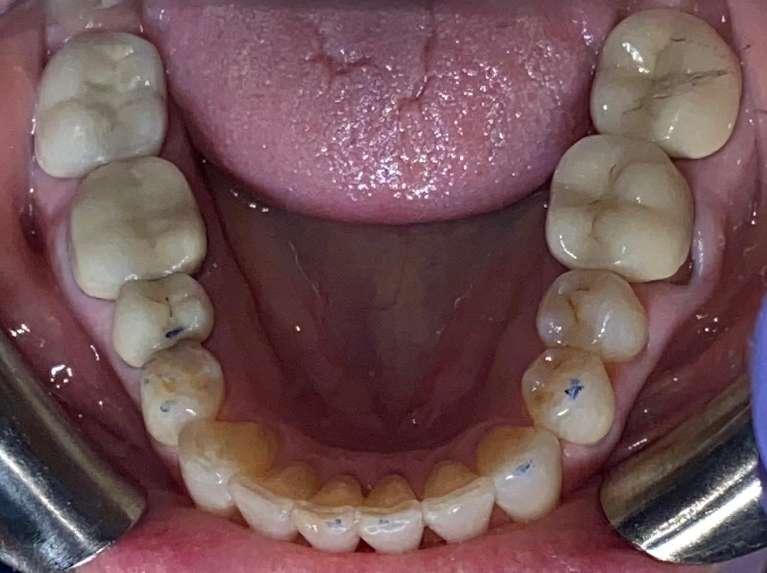

This case combined Invisalign, composite restorations, whitening and veneers to restore damage done from decades of grinding. Most dental offices would have placed crowns on all the back teeth, but with Invisalign treatment to set the bite, we were able to preserve more of the patients teeth while saving time and expense.